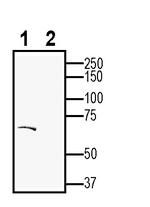

Dopamine Transporter (DAT) (extracellular) Polyclonal Antibody

Immunogen sequence: ESRRVSGRTYGAAR

Reconstitution: 25 uL, 50 uL or 0.2 mL double distilled water (DDW), depending on the sample size. The antibody ships as a lyophilized powder at room temperature. Upon arrival, it should be stored at -20C. The reconstituted solution can be stored at 4C for up to 1 week. For longer periods, small aliquots should be stored at -20C. Avoid multiple freezing and thawing. Centrifuge all antibody preparations before use (10000 x g 5 min).